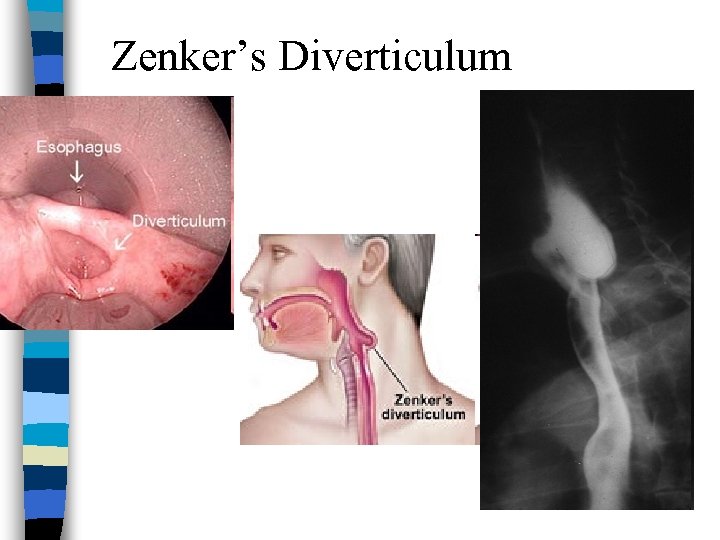

Zenker’s diverticulum n Posterior outpouchings of mucosa and submucosa through the cricopharyngeal muscle n Likely results from an incoordination between pharyngeal propulsion and cricopharyngeal relaxation n SX: Regurg, choking, protrusion in neck n TRT: surgery, stapling

Zenker’s Diverticulum